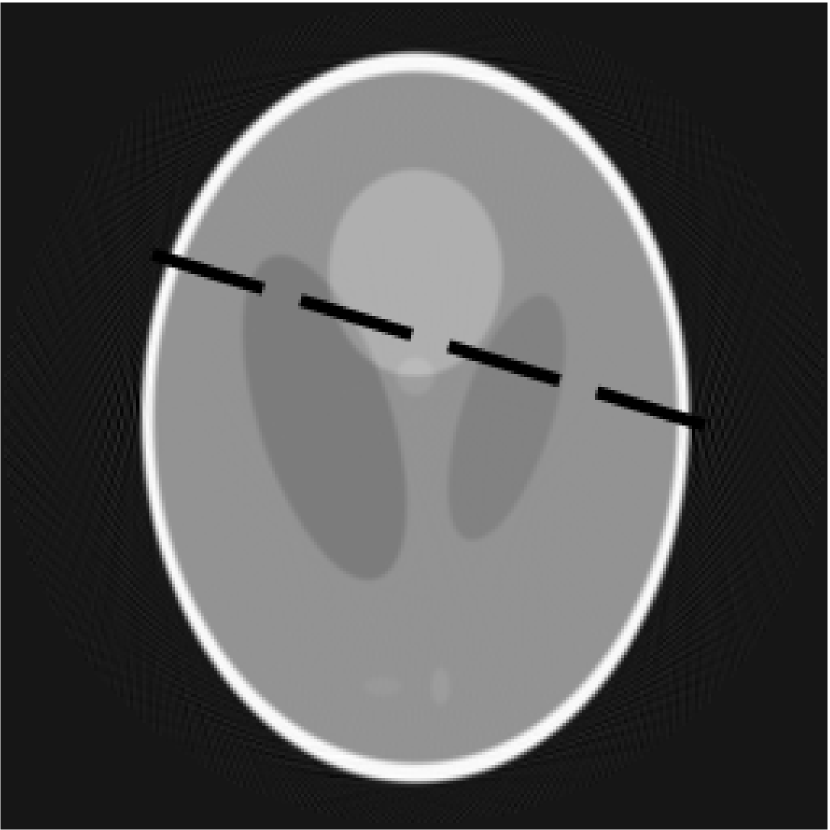

The simplest idea is to divide pixel-wise image, produced by the decomposition algorithm, by image obtained from the FDK. This gives a relative difference between images. An example of using this method is shown in figures 4a, 4b and 4c. FigureΒ 4a is a slice reconstructed by the FDK, figureΒ 4b - by the FDK-OD and figureΒ 4c shows a result of pixel-wise division of these 2 slices.

Refer to caption

(a)

(b)

(c)

Figure 4: Slices reconstructed with the FDK(4a) and FDK-OD(4b), result of pixelwise division(4c)

In practice, this approach has drawbacks due to several reasons. Angular decimation increases intensity of artifacts on the image background. Intensity of the background pixels is close to zero, so even small divergence leads to big relative difference. Noisy parts of image also present a serious problem. Decomposition stage uses low-pass filter for anti-aliasing and this flattens noise because it is connected to high frequencies. Thus, the simple division mostly shows a degree of similarity for the background artifacts and the noise, that isn’t so important for the reconstruction problem.